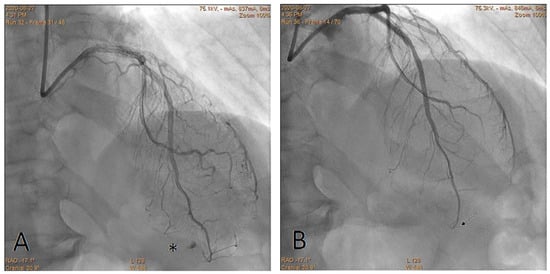

Embolization of Perforated Coronary Artery with a Fragment of Balloon Catheter (Cut Balloon Technique)—Multicenter Study

- Sobieszek, G.; Zięba, B. Balloon Fragment Technique Used to Close Distal Coronary Vessel Perforation. J. Invasive Cardiol. 2020, 32, E370–E372. [Google Scholar] [PubMed]

- Öcal, L.; Yılmaz, C.; Uysal, S.; Cerşit, S.; Zehir, R. Successful management of distal coronary artery perforation with the modified cut balloon technique during percutaneous coronary intervention. Anatol. J. Cardiol. 2022, 26, 66–68. [Google Scholar] [CrossRef] [PubMed]

- Alavi, S.H.; Hassanzadeh, M.; Dehghani, P.; Mehdipour Namdar, Z.; Aslani, A. A Novel Technique for Managing Guidewire-Induced Distal Coronary Perforation Using Coronary Balloon Pieces. JACC Case Rep. 2022, 4, 137–141. [Google Scholar] [CrossRef] [PubMed]

- Abdalwahab, A.; McQuillan, C.; Farag, M.; Egred, M. Novel economic treatment for coronary wire perforation: A case report. World J. Cardiol. 2021, 13, 177–182. [Google Scholar] [CrossRef] [PubMed]